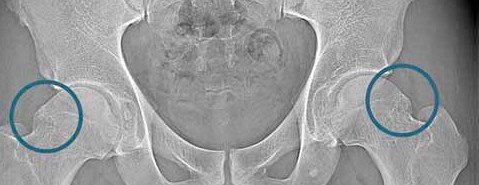

Istnieje wiele przyczyn dolegliwości bólowych stawu biodrowego, a jedną z nich jest konflikt udowo-panewkowy (FAI) - wyjaśnia ortopeda Rehasport Paweł Rybak. Problem ten został po raz pierwszy opisany w 2003 roku, jako powtarzający się stan nieprawidłowego kontaktu panewki z głową kości udowej, prowadząc do zmian degeneracyjnych i uszkodzeń chrząstki stawowej oraz obrąbka. Konflikt udowo-panewkowy jest spowodowany nieprawidłowym wzrostem kości, który występuje w obrębie głowy kości udowej, panewki lub obu na raz. Konflikt typu Cam występuje, gdy kostna deformacja pojawia się na granicy szyjki i głowy kości udowej. Ta guzowatość przeszkadza pełnemu obrotowi głowy kości udowej w panewce lub ocierać o obrąbek i chrząstkę znajdującą się wewnątrz stawu biodrowego, powodując jej uszkodzenie.

Statystyki podają, że Cam najczęściej występuje u młodych mężczyzn, znacznie rzadziej u kobiet. Konflikt typu Pincer występuje, gdy kostna deformacja wyrasta na krawędzi panewki. Wypukła guzowatość tworzy nawis pogłębiając w niektórych miejscach panewkę, co ogranicza obracanie się głowy kości udowej w panewce lub uszkadza obrąbek stawowy. Pincer występuje u kobiet w średnim wieku. Jednak wiele osób ma konflikt mieszany, czyli współistnieje typ Cam i Pincer.

Test tylnego konfliktu – pacjent leży na plecach ze stawem biodrowym umieszczonym na brzegu łóżka, lekarz odwodzi, a następnie wykonuje rotację zewnętrzną. W diagnostyce konfliktu udowo-panewkowego ważną rolę pełni obrazowanie. Zdjęcie rentgenowskie może jednoznacznie potwierdzić schorzenie, pokazując kostne deformacje na kości udowej lub/i w rejonie panewki. Ważnym badaniem jest rezonans magnetyczny artro (z podaniem kontrastu dostawowo), który pokazuje ewentualne uszkodzenia obrąbka stawowego.